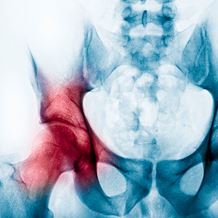

Usually present from birth and diagnosed in childhood, hip dysplasia can often escape detection until it is causing pain and discomfort later in adulthood. When the ball and socket joint of the hip are poorly connected, it causes a slight dislocation known as dysplasia. The socket is usually not deep enough to hold the ball-shaped femoral head in place. In time, this misalignment can go on to cause severe osteoarthritis as well as possible dislocation and labral tear. Symptoms can include hip pain, an unstable hip joint, limping and uneven leg length. Hip dysplasia tends to run in families and is known to be more common in firstborns, females and breech babies. If your doctor thinks you may have hip dysplasia after a physical examination, they are likely to suggest an X-ray or an MRI to determine the extent of the damage.

Babies are checked for hip dysplasia a few days after birth and shortly after again. At this age, the hip joint can be manipulated and repositioned using a brace before the cartilage turns into bone. After six months of age, arthroscopic surgery may be required to repair the hip and reposition the joint. If dysplasia is left untreated into adulthood, it can lead to severe joint deterioration from osteoarthritis. This would then require either realignment surgery (periacetabular osteotomy) or in extreme cases a total hip replacement to restore mobility and function.